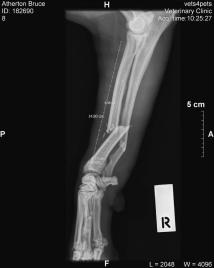

July was the first and only time the dogs have been out the front gate, the results of which was a broken Bruce. I’d left the front gate open for Linhda, again for the first time and something I’ve never done since, and then forgotten and let the dogs out the front to pee before bed. It wasn’t five minutes later that I realised, but they were already out. I found them a kilometre or so down the road. Domino and Tatyl jumped in the car, but Bruce wouldn’t come close. I figured he knew he was in trouble and so was staying back. I let him run home besides the car, and on the way home noticed he was limping. Then I realised he wasn’t using his right front let at all. Then I saw that it was actually dangling in the breeze and pissing out blood.

A midnight trip to the emergency vet room, followed by some work by an orthopaedic surgeon, resulted in a plate and 9 screws holding together his broken ulna and radius.

Broken ulna and radius.